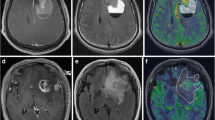

rCBV, molecular genetics and clinical characteristics. rCBV for each tumour is given as the mean±standard deviation of three independent observations. The arrow indicates tumours with rCBV above (high rCBV) and below the cut-off value of 1.59 (low rCBV). CR complete response (disappearance of all tumour, off steroids and neurologically stable or improved), PR partial response (50% or greater reduction in cross-sectional area, steroids stable or reduced, and neurologically stable or improved); MR minor response (>25 to <50% reduction in cross-sectional area, steroids stable or reduced, and neurologically stable or improved); PD progressive disease (25% or greater increase in cross-sectional area or any new tumour on CT/MR images and/or neurologically worse with steroids stable or increased); SD stable disease (all other situations); P primary tumour, R recurrent tumour

rCBV and outcome following PCV chemotherapy

Of the 37 patients, 33 had PCV chemotherapy following DSC-MRI (median 0.7 months, range 0.1–15.2 months), of whom 26 with primary tumours received PCV chemotherapy as the first oncology therapy, 6 with recurrent or persistent disease treated initially with radiotherapy received PCV as second oncology therapy, and 1 had PCV following radiotherapy and temozolomide. One patient with primary tumour had therapy switched to radiotherapy at the end of the first cycle because of reaction to procarbazine. The remainder received a median of four cycles of PCV (range one to six). Response to therapy was assessed in 32 patients (Fig. 4). Measured radiological changes and clinical factors permitted response assessment using standard criteria of Macdonald et al. [23] in all patients showing enhancement. However, in tumours showing no enhancement assessed using T2-weighted MR images, three showed radiological change in cross-sectional area of >25% to <50%, accompanied by clinical benefit; these were included in the minor response (MR) category. None of those showing enhancement had measured radiological change in this range. Response (i.e. complete, partial or minor; see Fig. 4 legend for definition) was seen in tumours with and without high rCBV. Similarly, non-responders (i.e. patients with stable or progressive disease) had either high or low tumour rCBV (Table 1, Fig. 4). Response was strongly associated with genotype; all 16 tumours with loss of 1p36 and 19q13 responded compared with 5 of 17 tumours with intact 1p36/19q13 (Chi2 P<0.001). Of the 16 responders in the 1p36/19q13 loss group, 14 had high rCBV. The five responders in the intact 1p36/19q13 group all had low rCBV and the four tumours with high rCBV failed to respond.

The relationship between rCBV, genotype, histopathology and survival following PCV in the series and in those with primary tumour is given in Table 2. The −1p/−19q genotype and low-grade pathology were associated with longer PFS and OS. Histopathology subtype was not significantly associated with outcome. Increased rCBV was only associated with short PFS and OS when adjusted for the −1p/−19q genotype. Tumours with intact 1p/19q and high rCBV (two grade III primary oligoastrocytoma, one grade II recurrent oligodendroglioma, one grade III recurrent oligoastrocytoma) were associated with shorter PFS and OS than tumours with intact 1p/19q and low rCBV or those with lp/19q loss and high rCBV (Fig. 5a,b). Similar findings were observed if primary tumour only were analysed (Fig. 5c,d). Compared with significant clinicopathological parameters, high rCBV was an independent prognostic factor for PFS when adjusted for 1p/19q status (Cox regression: PFS: hazard ratio 13.4, 95% CI 1.3–133; P=0.008) and for PFS and OS in patients with intact 1p/19q (Cox regression: PFS: hazard ratio 16.5, 95% CI 1.8–152.2; P=0.004; OS: hazard ratio 7.4, 95% CI 1.6–33.3; P=0.013).

rCBV and outcome following PCV chemotherapy: a, b all patients; c, d patients with primary tumour only; a, c progression-free survival; b, d overall survival.① Patients with tumours with low rCBV (<1.59) and loss of 1p36 and 19q13 (all n=2, primary n=2).② Patients with tumours with high rCBV (>1.59) and loss of 1p36 and 19q13 (all n=15, primary n=12).③ Patients with tumours with low rCBV (<1.59) with intact 1p36 and 19q13 (all n=12, primary n=10).④ Patients with tumours with high rCBV (>1.59) and intact 1p36 and 19q13 (all n=4, primary n=2)